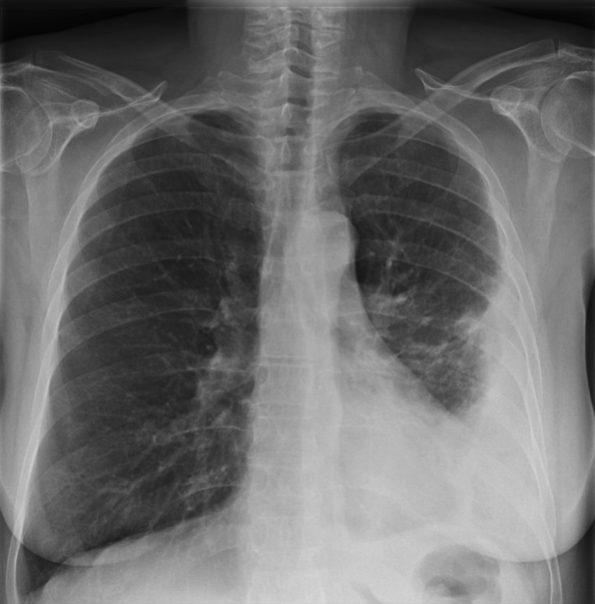

A neonate born at 28 weeks of gestation via C section presents with tachypnea, nasal flaring, grunting, and cyanosis. A chest X-ray shows a ground-glass appearance with air bronchograms. What is the most likely cause of the neonate’s respiratory distress?